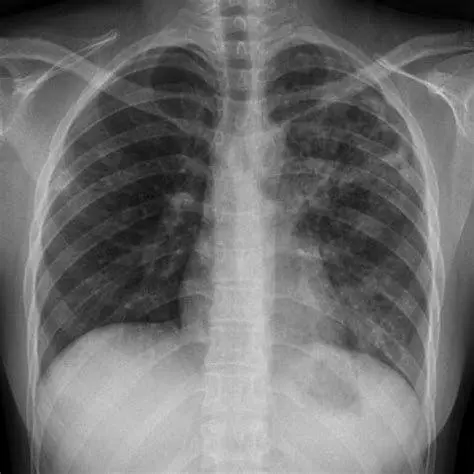

- Rontgen Dada (X-Ray): Melihat adanya bercak putih atau lubang (kavitas) pada organ paru-paru.